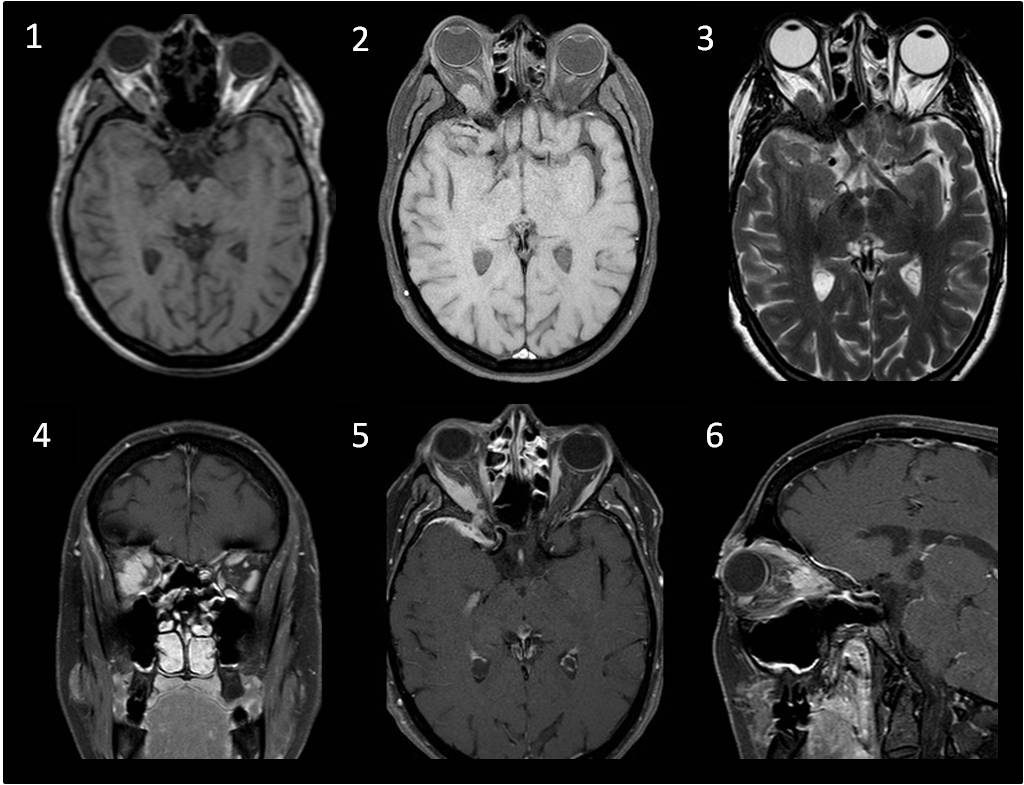

FIGURAS 1, 2: Secuencias SE T1, sin y con supresión grasa donde se observa tumoración de partes blandas, intraconal adyacente al músculo recto externo.

FIGURA 3: Secuencia SE T2, que muestra hipointensidad de señal de la lesión.

FIGURA 4, 5: Secuencias T1 con supresión grasa y administración de Gd. Marcada captación de contraste homogéneo, que se extiende al espacio extraconal.Afecta a toda la longitud del músculo, sin respetar la inserción.